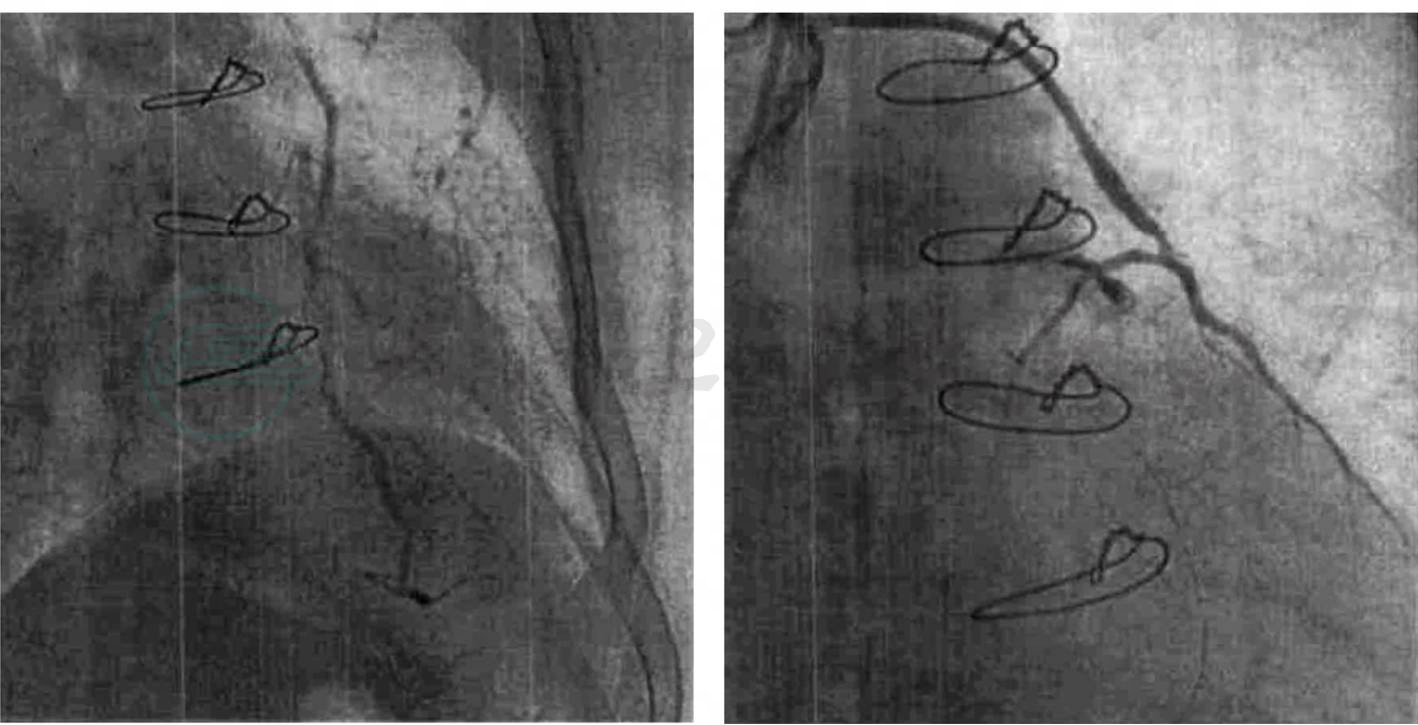

BP 130/70mmHg,HR 70次/分,律齐,心脏杂音同前述。双肺呼吸音清楚,无干湿性啰音。无颈静脉怒张、肝脾肿大和下肢水肿。入院后完善了实验室和影像学检查,心脏远达片示:双肺纹理正常,主动脉结凸,肺动脉段平直,左心房稍大,心胸比0.51。心脏MRI检查进一步明确了心肌肥厚的范围和程度:室间隔大部及前壁基底段增厚,室间隔近段最厚(25~26mm),左室流出道有收缩期梗阻征象。虽然单纯的梗阻性肥厚型心肌病就能够解释患者心绞痛的发作,但是此患者有明确的冠心病危险因素,是否还有别的病因?因此,为了判断有无合并冠心病,2005年9月13日进行了冠状动脉造影和左室造影,结果显示:冠状动脉双支病变,累及前降支和右冠状动脉,前降支近端斑块,中端近段80%局限偏心狭窄、中段管状偏心狭窄60%,远端管状狭窄70%,第一对角支开口局限偏心狭窄90%;右冠状动脉近端和中端均散在斑块,左室后侧支中段狭窄70%。左室造影显示(图2):左室流出道压差70mmHg。

图2 左室造影结果(2005年9月13日)